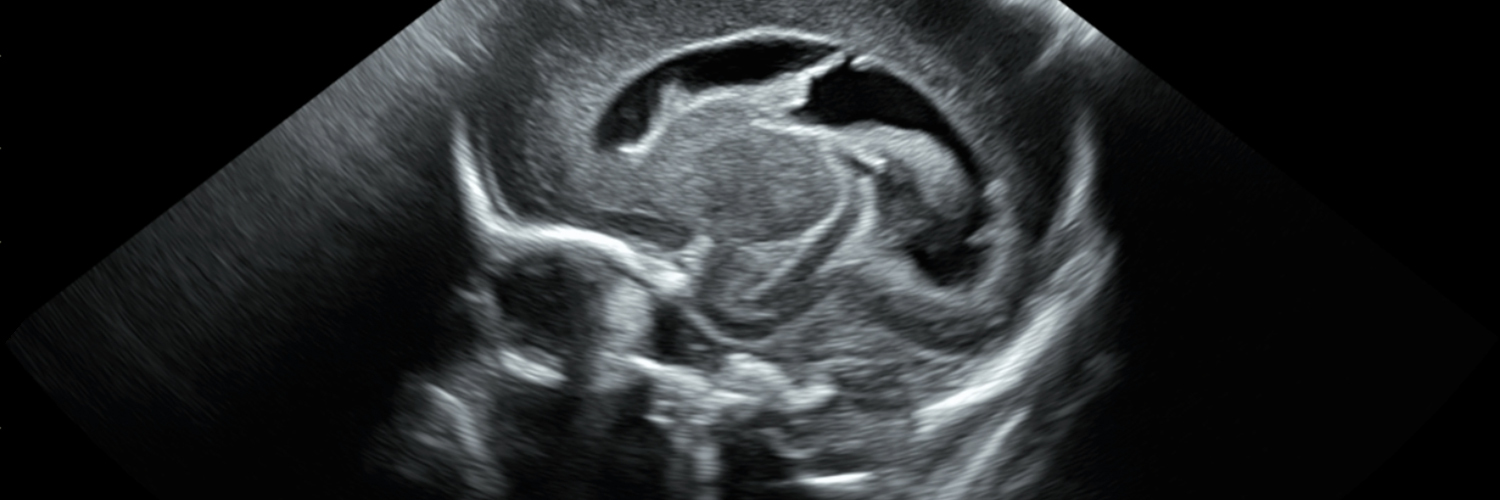

With SonoSim, your next practice session is never limited by a machine, a schedule, or a lab. Just plug in, scan real pathologies, and build skills anywhere your day takes you. ✨